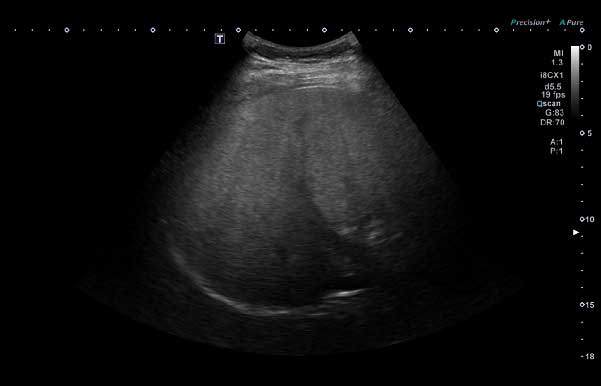

13세 남아의 간 초음파 사진. 간이 정상보다 밝게 보이고 깊은 부위가 잘 관찰되지 않는 모습으로, 지방이 축적될 때 나타나는 전형적인 모습. 중등도 지방간 소견./사진=서울대병원 영상의학과 최재원·소아청소년과 심정옥 교수 도움

◇초음파로 확인… 진행 시 간경화 위험

소아 지방간이 의심되면 혈액 검사와 문진, 신체 진찰 후 영상 검사를 시행한다. 가장 기본은 복부 초음파 검사로, 이를 통해 간에 지방이 얼마나 축적돼 있는지 확인할 수 있다. 경우에 따라 간 섬유화(딱딱한 흉터 조직)정도를 평가하는 탄성 초음파나 MRI(자기공명영상) 검사를 추가하기도 한다. 간 조직 검사는 제한적인 경우에만 시행된다.